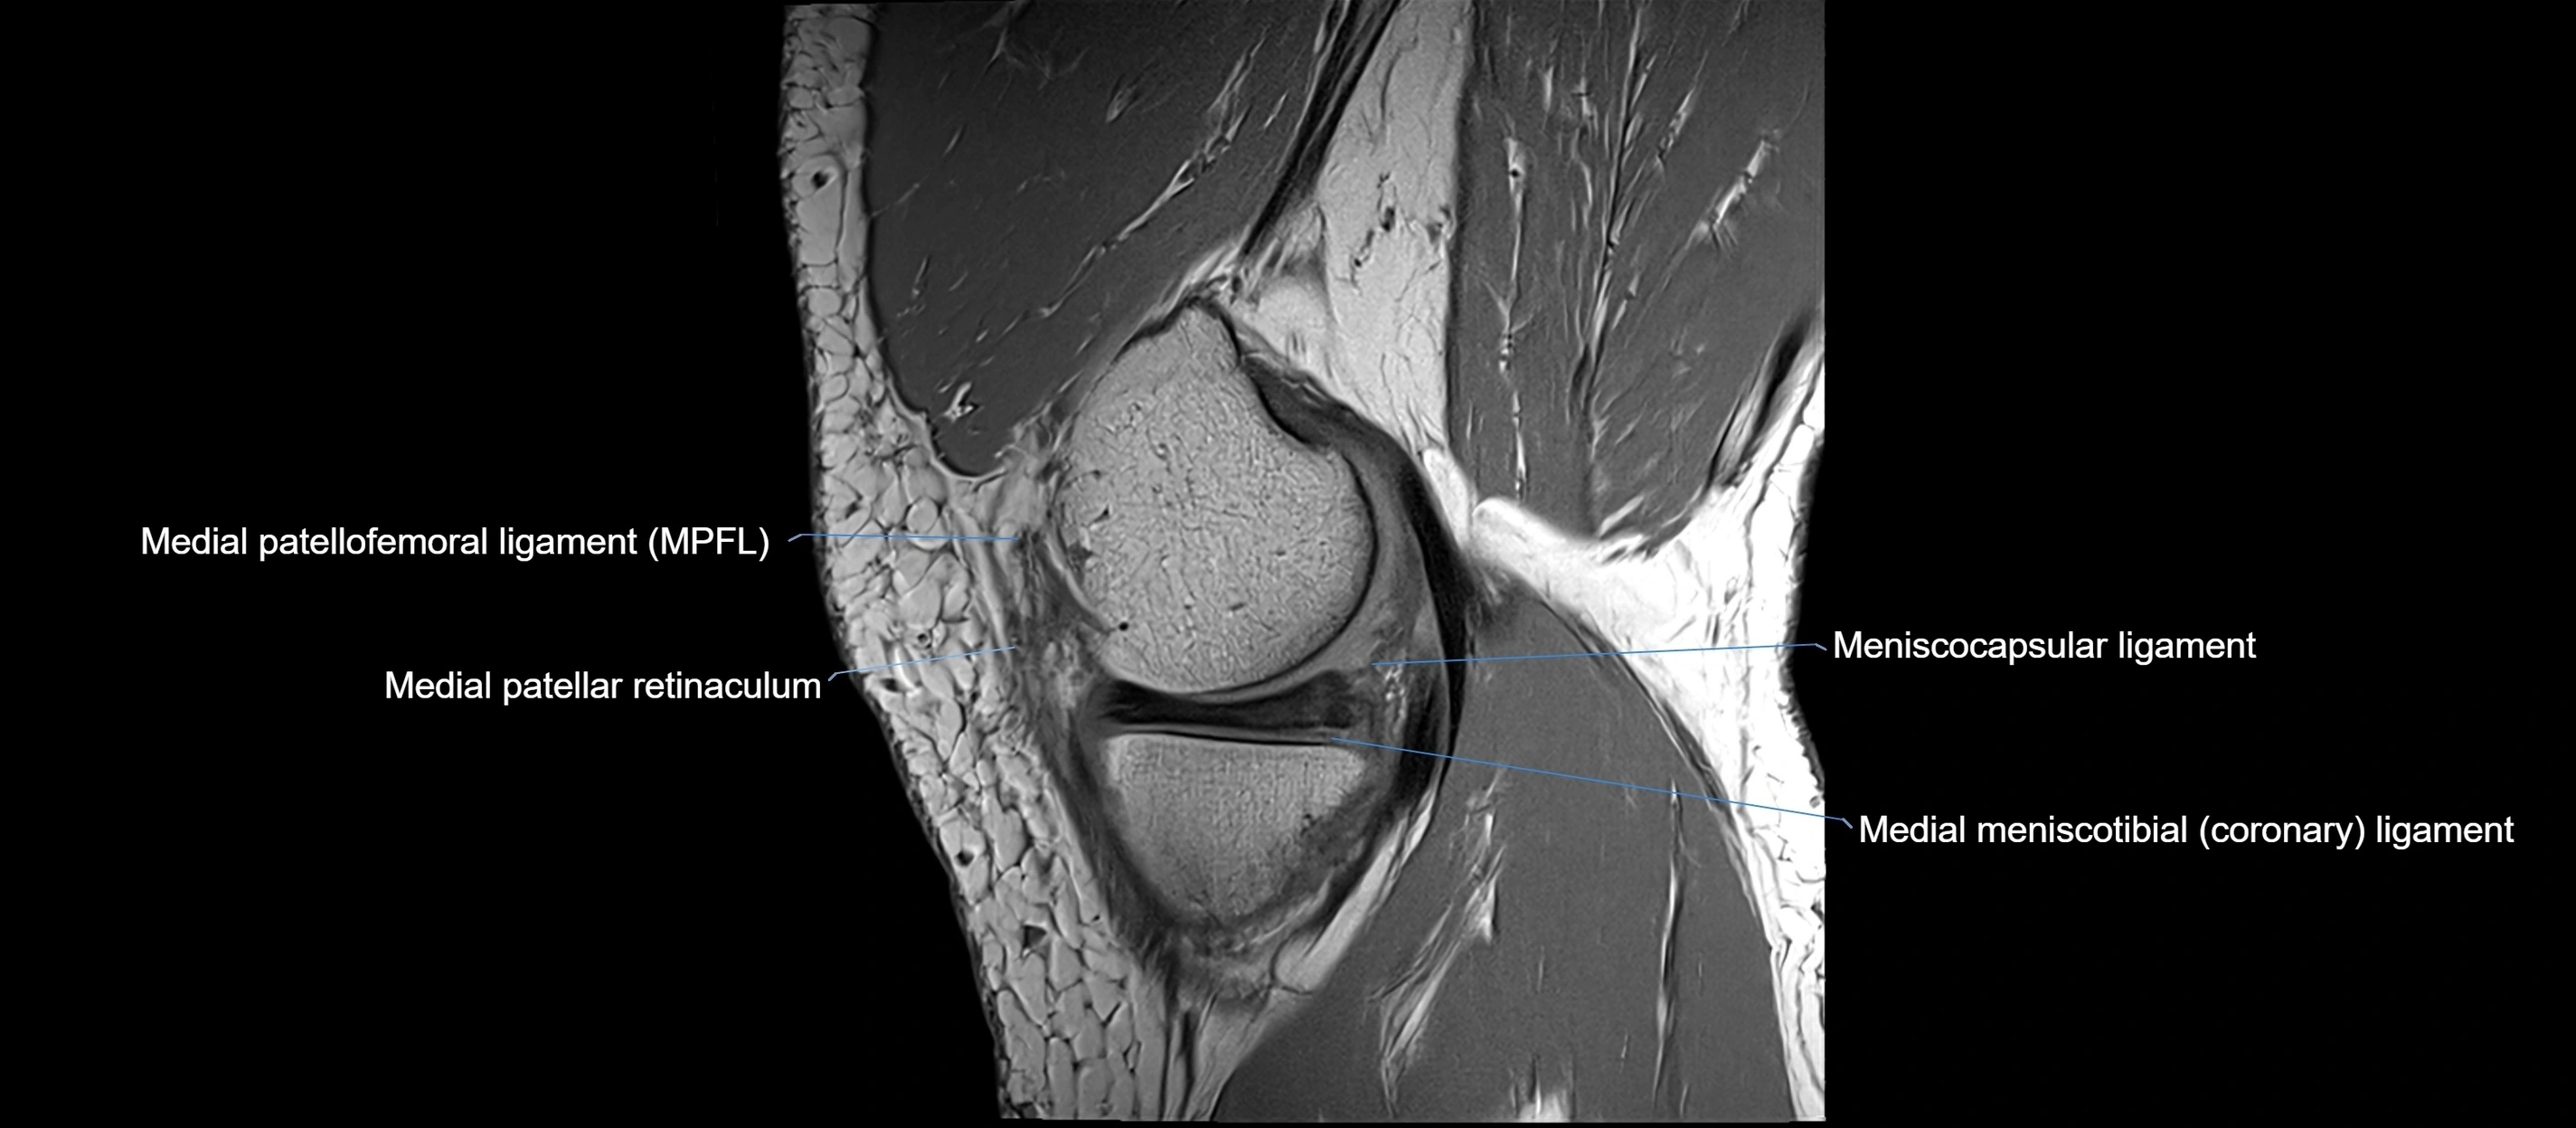

MRI images

image